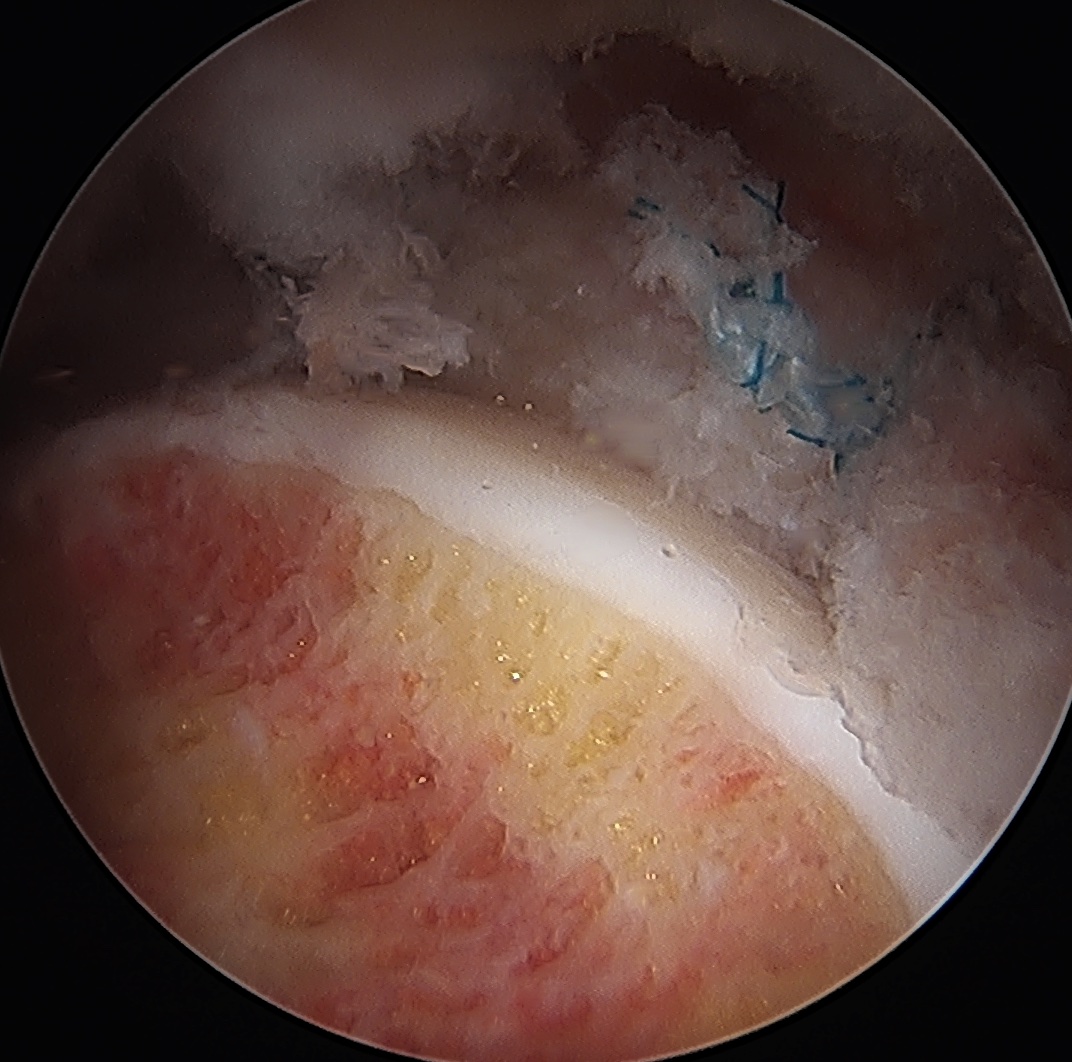

Labral repair

Options

- knotted versus knotless anchors

- straight versus curved

Must avoid intra-articular penetration

Labral debridement

- for degenerative / irreparable / ossified labrum / failed labral repair